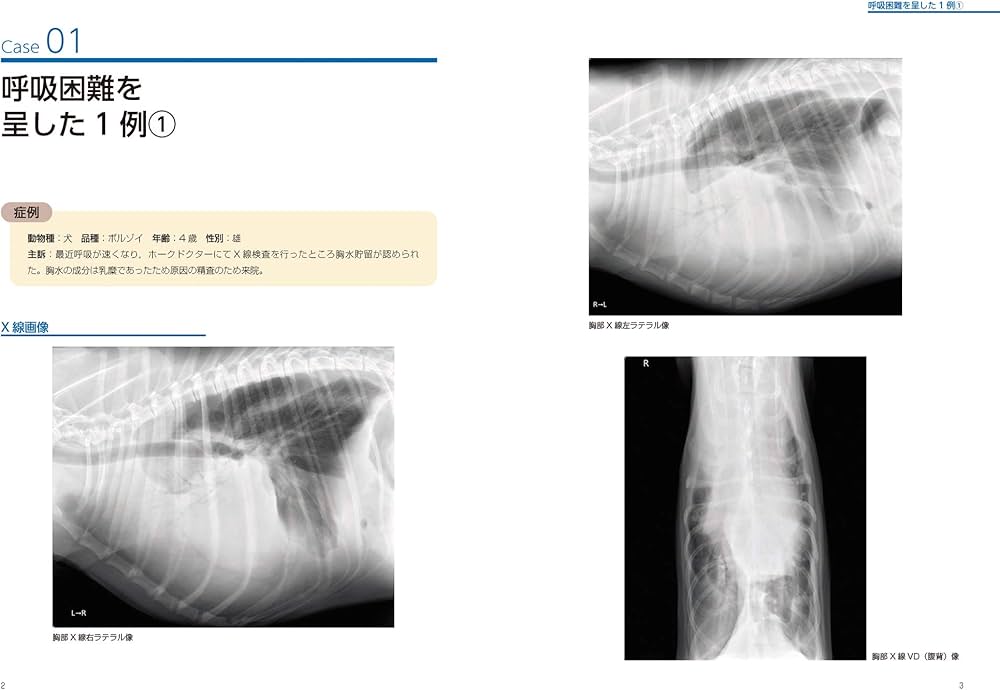

犬と猫の胸部画像診断に関する専門的なマニュアル。- タイトル: BSAVA 犬と猫の胸部画像診断マニュアル- 出版社: NEW LLL PUBLISHER- 言語: 日本語- 内容: 犬と猫の胸部画像診断に関する専門的な情報を提供するマニュアルご覧いただきありがとうございます。